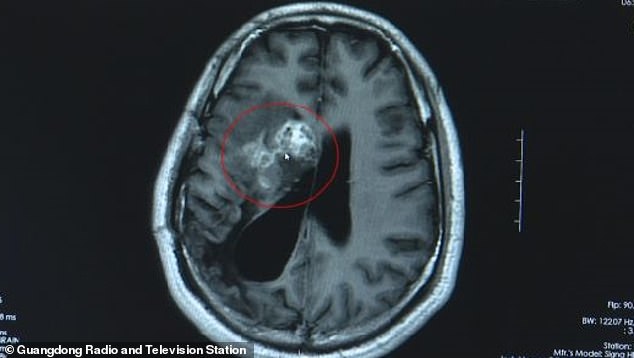

Την πρώτη φορά που πήγε στο νοσοκομείο το 2007 οι γιατροί διέγνωσαν κακοήθη όγκο και ξεκίνησε τις χημειοθεραπείες.

Η κατάσταση του δεν βελτιωνόταν αλλά ούτε και χειροτέρευε και τα χρόνια περνούσαν μέχρι που κάποιος γιατρός ύστερα από μια μαγνητική εγκεφάλου διαπίστωσε πως ο κ. Γουάνγκ δεν έχει όγκο αλλά κάποιο παράσιτο μέσα στον εγκέφαλο του.

Ο άνδρας μπήκε στο χειρουργείο και ύστερα από μια επέμβαση 2 ωρών οι γιατροί κατάφεραν να βγάλουν την ταινία (το παράσιτο) από το κεφάλι του.

Οι γιατροί διέγνωσαν ότι είχε πάθει «σπαργάνωση» από τα σαλιγκάρια. Η σπαργάνωση μπορεί να είναι αποτέλεσμα κατανάλωσης μολυσμένου νερού ή κατανάλωσης ζώου-ξενιστή του παρασίτου, όπως βατράχι ή φίδι. Πλήττει συνήθως τον εγκέφαλο ή τα μάτια.